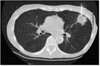

1

Not at all

2

3

4